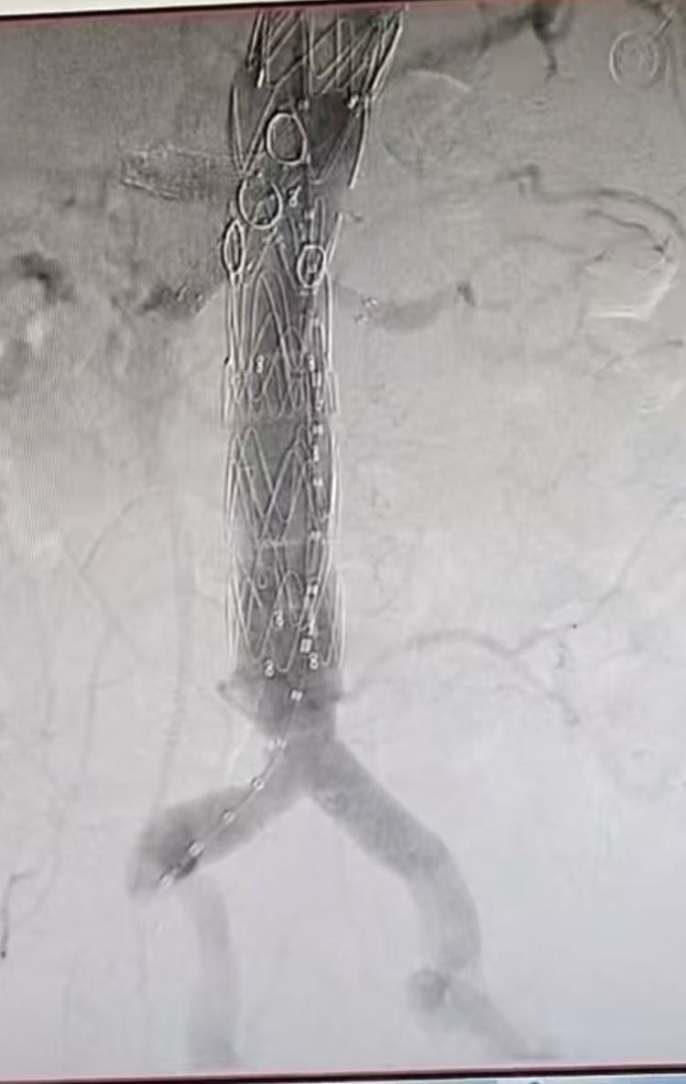

介入开窗手术治疗前后图片对比

手术当天,团队成员分为两组同步开展操作,一组建立手术通路(右腋动脉及右股动脉),一组改装支架,主体支架经右侧股动脉入路,被精准输送至病变部位,部分释放并顺利展开腹腔干、肠系膜上动脉外分支。

手术团队通过导管导丝操作技术,依次对腹腔干、肠系膜上动脉、双肾动脉进行精准选入并植入支架,成功完成对重要内脏分支动脉的血运重建。最后,一枚大动脉覆膜支架被精准植入胸降主动脉,与主体支架完美衔接,将夹层动脉瘤完全隔绝于血液循环之外,彻底消除破裂风险。术后最终造影结果显示:夹层动脉瘤隔绝彻底,无内漏发生,腹腔干、肠系膜上动脉、双肾动脉等四支血管血流通畅。